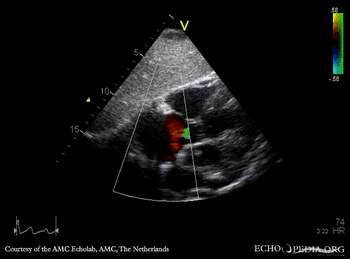

Case 47

| A4CH: ASD type II | A4CH: enlargement of right ventricle and right atrium |